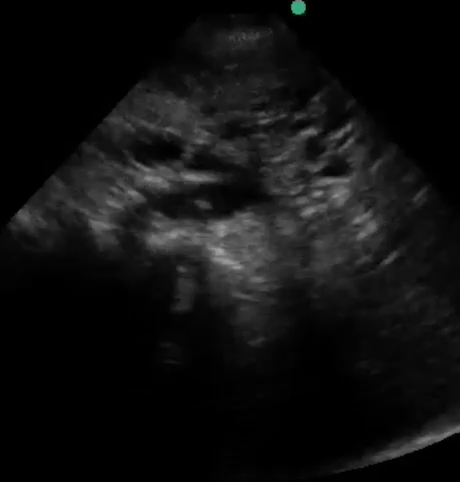

Point-of-care sonography was performed in order to assess volume status and the following representative image was obtained